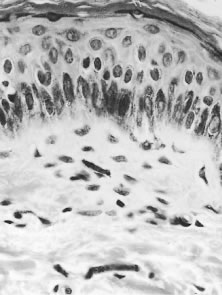

The earliest changes in the skin in onchocerciasis are mild and are often limited to a perivasculitis.14 In more heavily infected persons, microfilariae can be found, especially at the epidermal-dermal junction (Fig. 7). Live microfilariae are usually not surrounded by inflammatory cells.

Fig. 7. Microfilaria lying in the dermis. Although it has been cut into a number of sections, it is clearly recognizable, because the nuclei of the microfilaria are much smaller than those of the host cells. The absence of an inflammatory infiltrate around the microfilaria is characteristic (hematoxylin-eosin, ×700).

Later changes include hyperkeratosis, acanthosis, and parakeratosis, with an increase in inflammation and fibrosis. Dermal collagen is disrupted by the deposition of increasing amounts of mucin ground substance and by fibrous scar tissue. With more advanced fibrosis and inflammation, microfilariae become less common in the superficial dermis and are found mainly in the deeper layers. Ultimately, the dermis becomes fibrotic and is covered by a thinned and atrophic epithelium. There are areas of depigmentation and hyperpigmentation (Fig. 8). Some patients have a much more severe, reactive onchodermatitis, often confined to one limb. This was first described in Yemen and is called “sowda,” or black limb. Here, the most prominent histologic change is an extensive infiltrate of plasma cells.14 Microfilariae are seen occasionally in the deep dermis or in skin snips. These patients have a high cellular immune response to onchocercal antigens, which is suppressed if their disease becomes generalized.